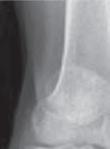

Rycina 17.82.

Uszkodzenie tętnicy podkolanowej wskutek złuszczenia nasady bliższej kości piszczelowej (S-H 1). Zagrożenie rozwojem zespołu przedziałów powięziowych jest poważne.

Rozpoznanie

Objawy złamania to silny ból uniemożliwiający stanie i chodzenie, zniekształcenie obrysów stawu kolanowego przez krwiak i różnego stopnia przemieszczenie nasady kości piszczelowej. Należy dokładnie zbadać stan ukrwienia i unaczynienia kończyny pod kątem objawów uszkodzenia tętnicy podkolanowej i nerwu strzałkowego. Trzeba ocenić bolesność uciskową oraz napięcie w przedziałach powięziowych podudzia: przednim, bocznym, tylnym powierzchownym i tylnym głębokim. U pacjentów z podejrzeniem wzmożonego ciśnienia wewnątrzprzedziałowego należy wielokrotnie powtarzać badanie ukrwienia i unerwienia kończyny, a w razie zaistnienia wskazań wykonać bezpośredni pomiar ciśnienia w przedziałach. Powinno się zawsze podejrzewać możliwość uszkodzeń więzadłowych współistniejących ze złamaniem. Badania obrazowe to RTG w pozycji AP, bocznej i skośnej. Wykonanie badania TK może być konieczne w celu pełnej oceny rozległości

złamania. W przypadku podejrzenia uszkodzenia tętnicy podkolanowej należy wykonać angio-TK lub arteriografię.